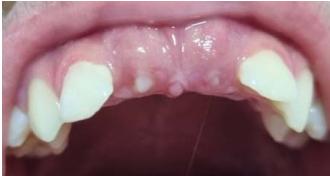

Uma criança de 11 anos de idade, 32 kg, apresenta queixa de demora de erupção dos incisivos permanentes superiores. Observe o aspecto clínico e radiográfico do caso descrito e julgue os itens a seguir.

Apenas em um terço dos casos, dentes supranumerários na dentição decídua são seguidos por um dente supranumerário na dentição permanente.